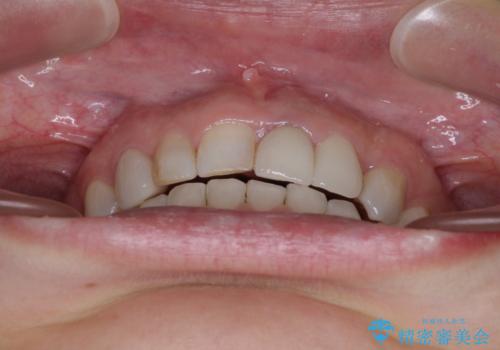

診察したところ、上顎前歯に過剰歯があることで上顎歯列が大きくなり、上下の歯が奥歯の一部でしか咬み合っていない状態でした。

咬み合わせ改善のため、前歯の過剰歯を抜去し、ワイヤー矯正にて歯列と咬み合わせることとしました。

上下非接触の咬み合わせは、舌突出癖によるところが大きく、トレーニングを行いながら治療を進めていきました。

なかなか突出癖が改善できず、過剰歯を抜歯したスペースを閉じるまでに時間がかかりました。

舌突出癖の改善は、治療期間や仕上がりに大きな影響を与えるため、しっかりとトレーニングすることが大切です。